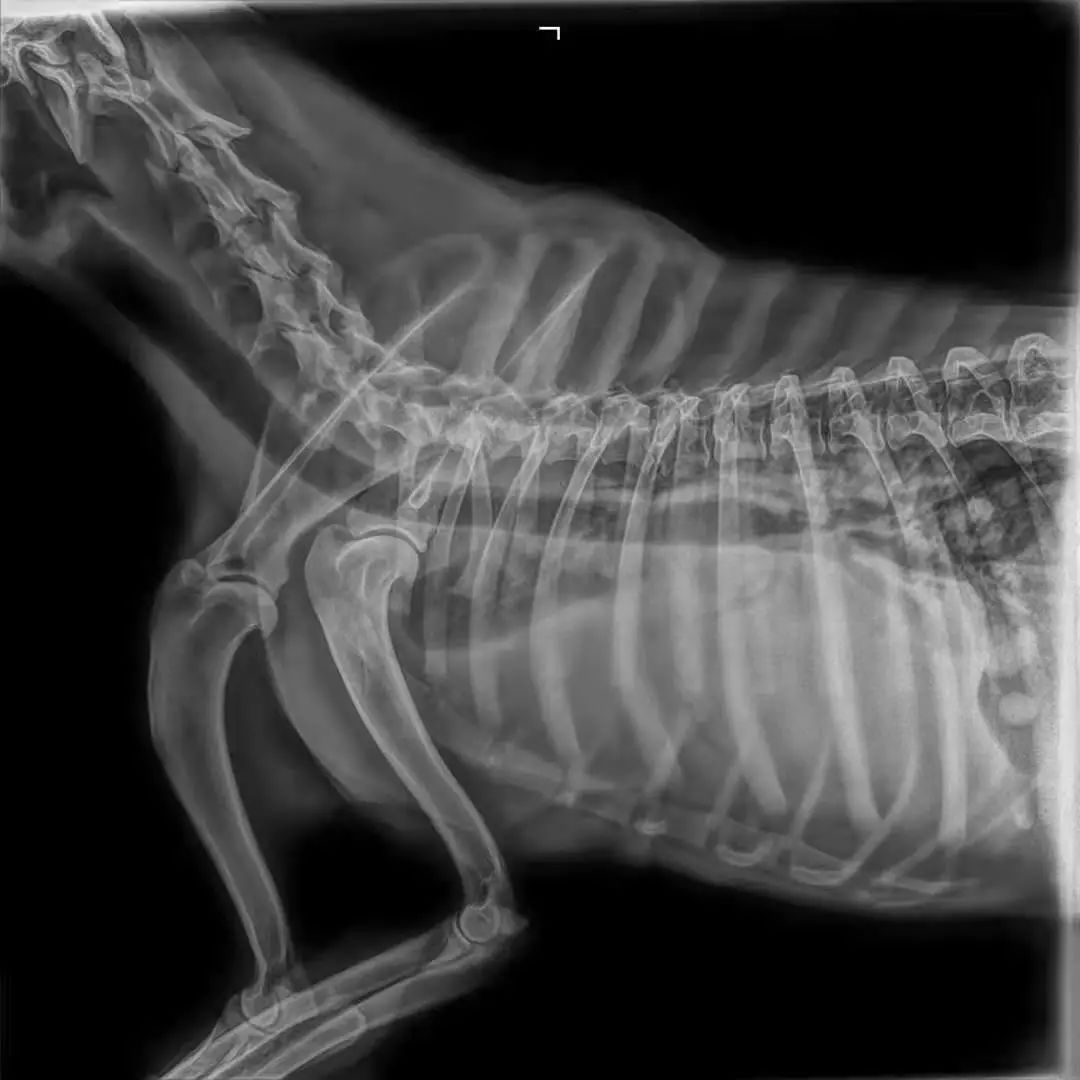

家长说动物干呕了二十天左右,不爱吃饭来就诊,但实际症状为咳嗽,消瘦,当触诊到腹部一个拳头大乳腺肿瘤的时候,开始怀疑可能乳腺肿瘤发生转移,DR,显示胸腔肿物,胸腔积液,才五岁.....尽早绝育,定期体检很重要↓↓